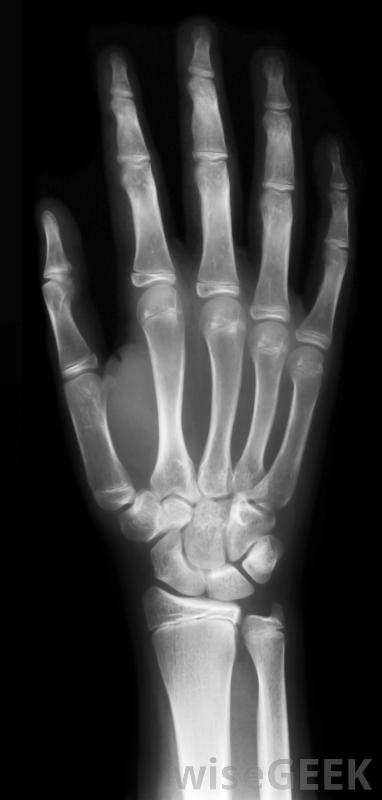

手的X光。

传统的X光通过测量被检测物体吸收的X光量来创建图像。在医疗使用中,骨骼在X光片上比皮肤或器官更容易看到的原因是骨骼的成分吸收了更多的X光,检测受检物体的辐射反射。